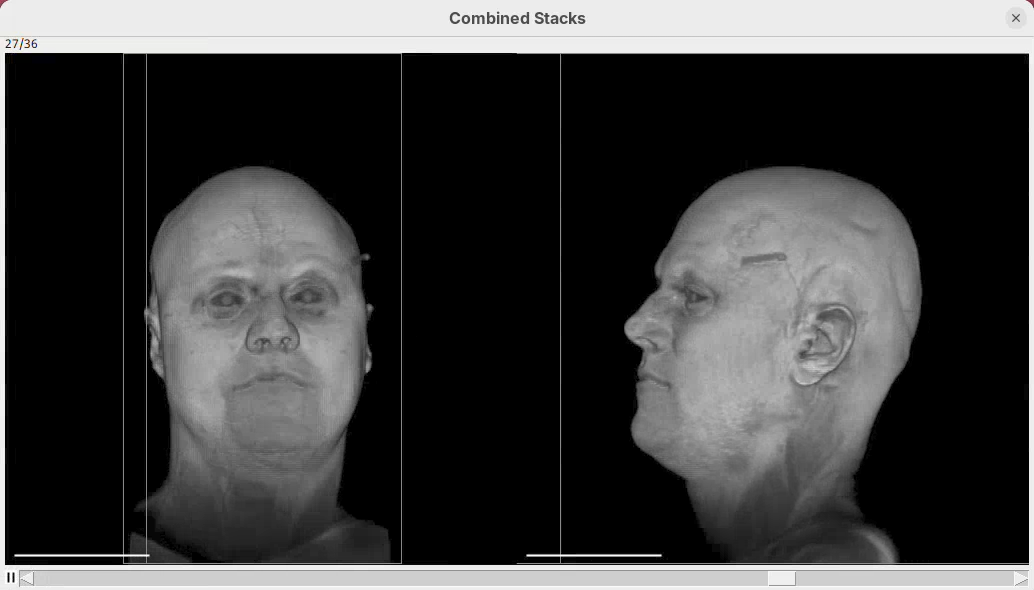

The left head is the one without easing (linear transition) and the right head is the animation with easing. Note how the right head accelerates the rotation at the beginning, turning much faster, and then decelerates towards the end of the rotation. Both end the rotation at the same time. Play both animations side-by-side to see the difference (it’s very clear, once you see it).